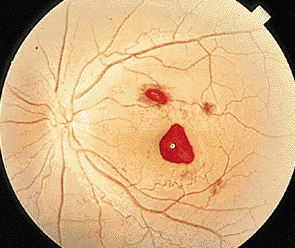

對于很多患者而言,玻璃體變性主要原因就是隨著年齡不斷增加,新陳代謝不斷變緩,使得玻璃體自身變性。比如像星狀玻璃體變性,常常見于50歲以上,不過它只是引起視力的不適,并不會導致視力下降。因為玻璃體內新陳代謝緩慢,而出現了含鈣的脂質白色小球。而玻璃體變性中更為嚴重的是出現液化現象,特別是閃輝性玻璃體液化,由于嚴重眼外傷和手術后眼內出血導致的玻璃體或前房會出現無數黃白色和其他顏色的膽固醇結晶。

對于玻璃體混濁這樣復雜的癥狀,一般的眼科醫(yī)院無法根治,由于眼睛玻璃體的特殊性,目前尚無有玻璃體變性的特效藥,只能經過長期的治療和鞏固,使得玻璃體不會出現其他病變。所以對于病情較為嚴重的玻璃體變性患者而言,就像因為變性引發(fā)的視網膜剝離或玻璃體出血等等,這些會出現視力嚴重減退,眼睛發(fā)紅、疼痛、畏光等等,一定要到專業(yè)的眼科醫(yī)院進行醫(yī)治,比如在廈門眼科醫(yī)院的眼底???,常年來除了眼底病之外,玻璃體變性治療領域在全國也是處于領先位置。